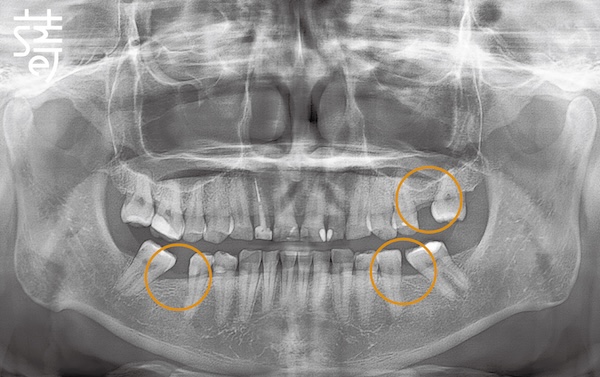

將牙齒重新排列整齊,調整上下咬合,把原本傾倒的第二大臼齒推回正確位置,為後續植牙和假牙重建打好基礎。

Teeth were realigned, the bite adjusted, and the previously tilted second molars repositioned, laying a solid foundation for implants and prosthetics.

第二階段:植牙重建缺牙區 Stage Two: Implants for Missing Molars

針對缺牙已久的後牙區進行植牙,恢復後牙支撐,避免整體咬合繼續崩塌,讓口腔受力更均衡。

Implants were placed in the long-missing molar areas to restore support, prevent further bite collapse, and balance oral forces.